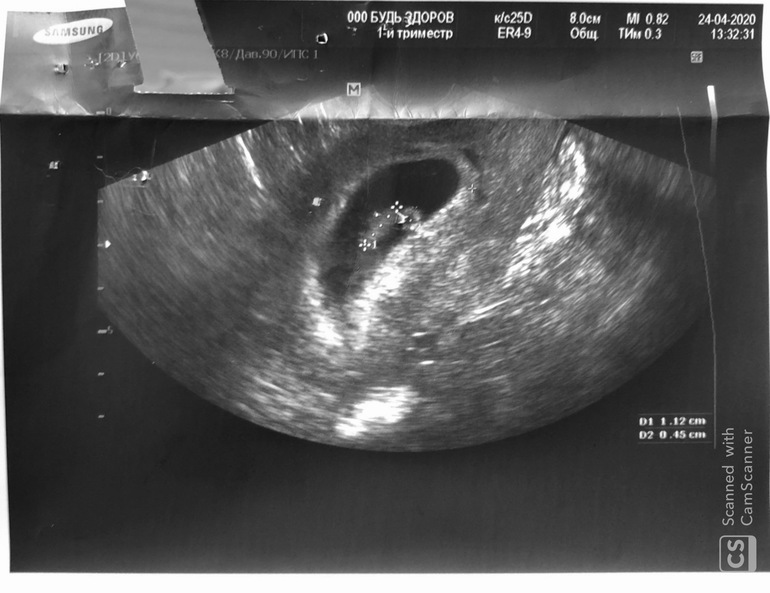

УЗИ, КТГ, доплер24 апреля сходила на УЗИ. Срок 7 недель 3 дня.

Плодное яйцо диаметром 3,2 см;

Желточный мешочек 45 мм;

КТР - 11 мм;

Печально, нашли ретрохориальную гематому примерно 5 мм.. ((( Сказала свечи Папаверин два раза в день на протяжении двух недель и увеличить дозу магне Б6.